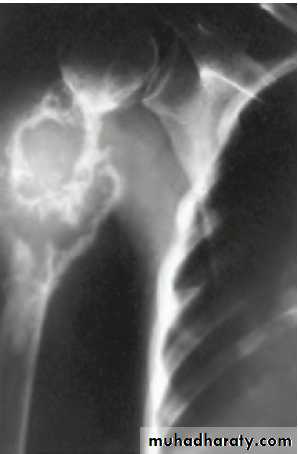

Lymph node and blood-borne metastases of thyroid cancer occur primarily to bone and lung and may be the mode of presentation